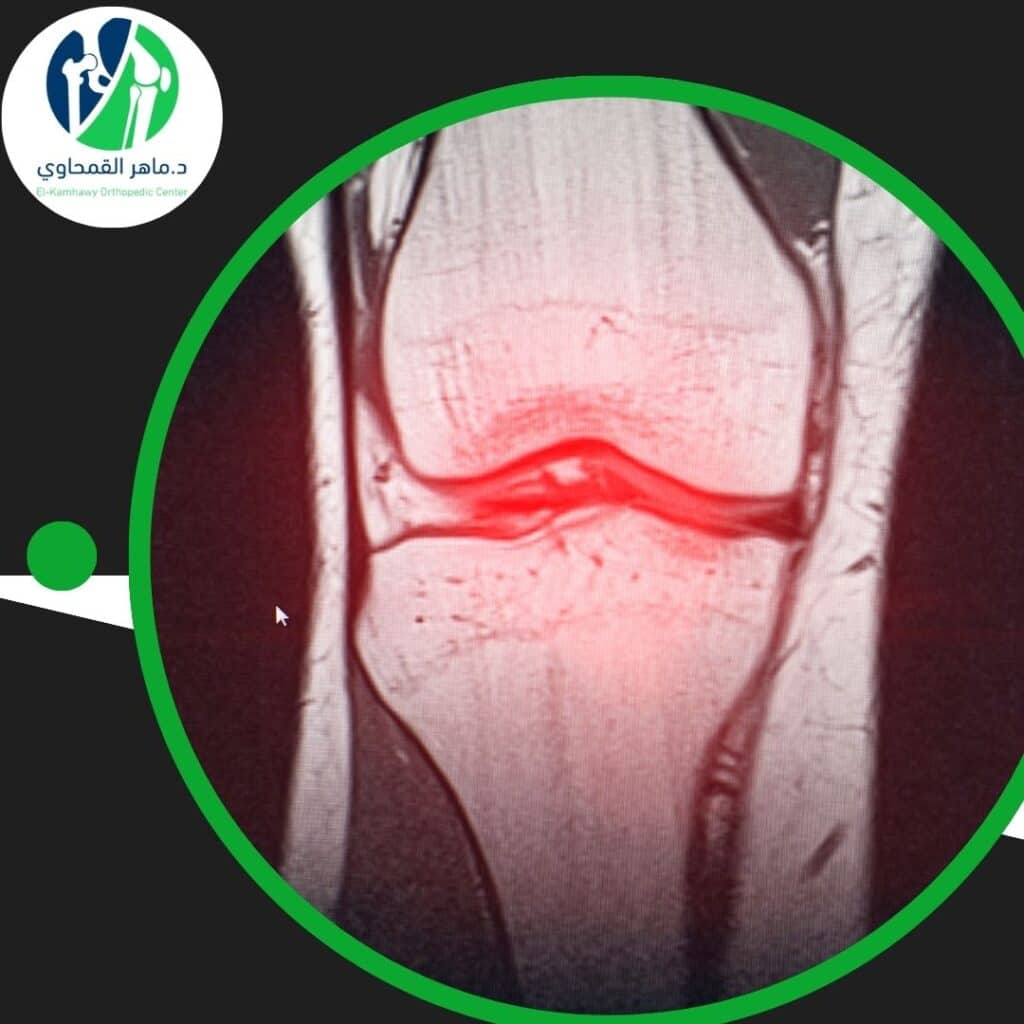

- الرنين المغناطيسي (MRI): وهو الأداة الأهم لتحديد موضع الانزلاق، ودرجة بروز الغضروف، ومدى الضغط على الأعصاب.